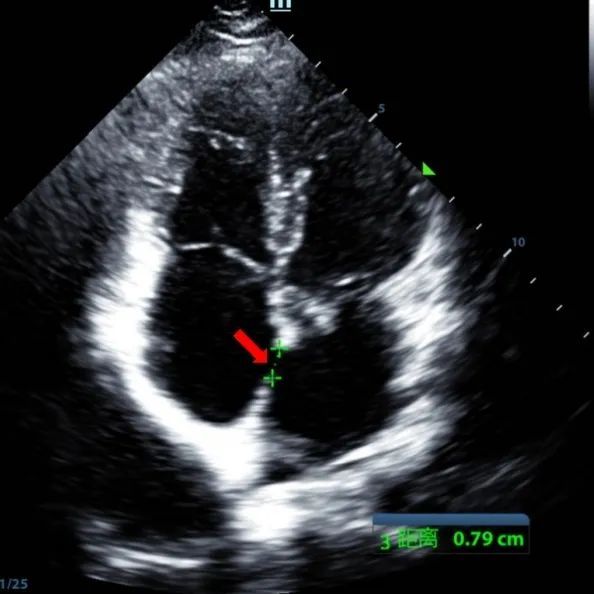

Secundum ASD (7.5〜7.9mm) の9歳の男性は、MemoSorb BDASD-I 12 mmオクルーダーおよび12Fデリバリーシステムを使用して治療されました。 手順前に合併症や併存症は見られませんでした。

Serial echocardiographic follow-ups showed stable device position and favorable cardiac remodeling. Gradual degradation confirmed the occluder's long-term safety and efficacy.